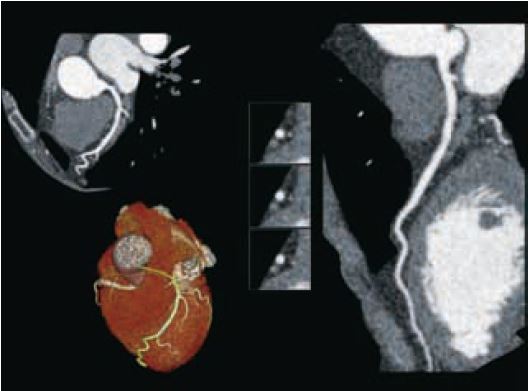

Наші типові пацієнти для обстеження КТА коронарних судин тепер отримують субмілізівертні дози опромінення з відмінною якістю зображення (рис. 8, 9). У молодих радіочутливих пацієнтів тепер ми можемо виконувати сканування значно нижче 0,5 мЗв, щоб відповісти на клінічне запитання (рис. 10). Таким прикладом є дослідження аномальних коронарних артерій, де справді все, що потрібно, — анатомічний огляд.

Рис. 9 Кт-коронарографія. DLP 30 (0,4 мЗв).

Рис. 8 КТ-ангіографія коронарних судин. ІМТ 26. Критичний стеноз LAD (стрілка). Доза 0,8 мЗв